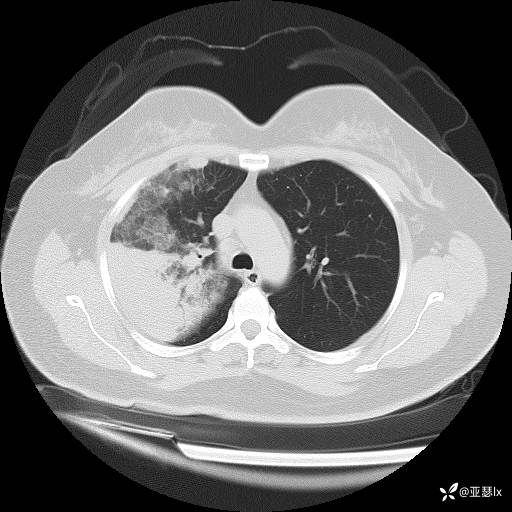

影像学:

诊断依据:1.社区发病;2.病史及体征:咳嗽、发热等急性感染表现;查体:右肺可闻及湿罗音,触觉语颤增强;3.实验室检查:感染指标明显升高;影像学:右肺实变影。

鉴别诊断:1.感染性:细菌、分枝杆菌、病毒、真菌病原体鉴别。

2.异常液体:肺出血?

3.肉芽组织:机化性肺炎?结节病?嗜酸性粒细胞性肺炎?类脂性肺炎?

4.其他:肿瘤?肺梗死?